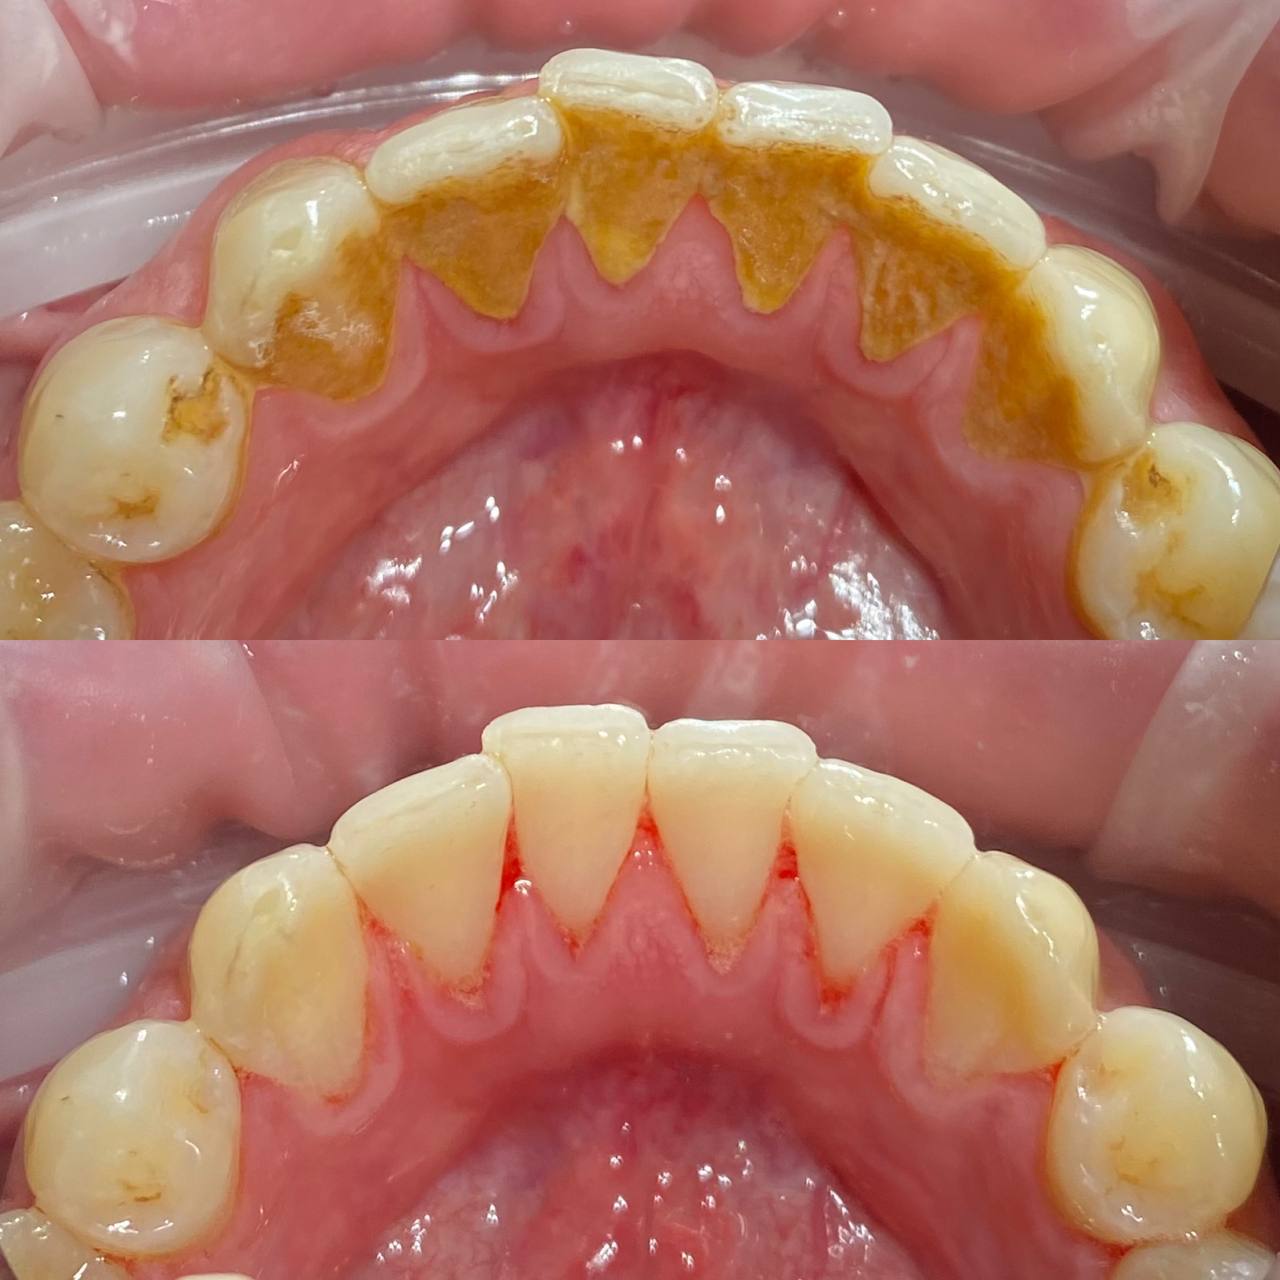

Даже если вы хорошо чистите зубы дома, на зубах со временем скапливается налет. А также на зубах есть труднодоступные места, которое вы не прочищаете. Поэтому нужно приходить на профгигиену в клинику не реже 1 раза в 6 месяцев. Очищение налета, удаление зубного камня, укрепление эмали — все это профессиональная гигиена. На сегодня это лучший способ защитить зубы от кариеса и сохранить десны здоровыми.

Процесс включает несколько этапов:

• Удаление зубного камня с помощью ультразвука;

• Очистка труднодоступных участков с использованием порошкового оборудования Air Flow;

• Полировка зубов специальными пастами, придающими эмали гладкость и блеск;

• Завершение процедуры нанесением реминерализующего состава для укрепления зубов.

• обучение домашней гигиене и подбор средств.